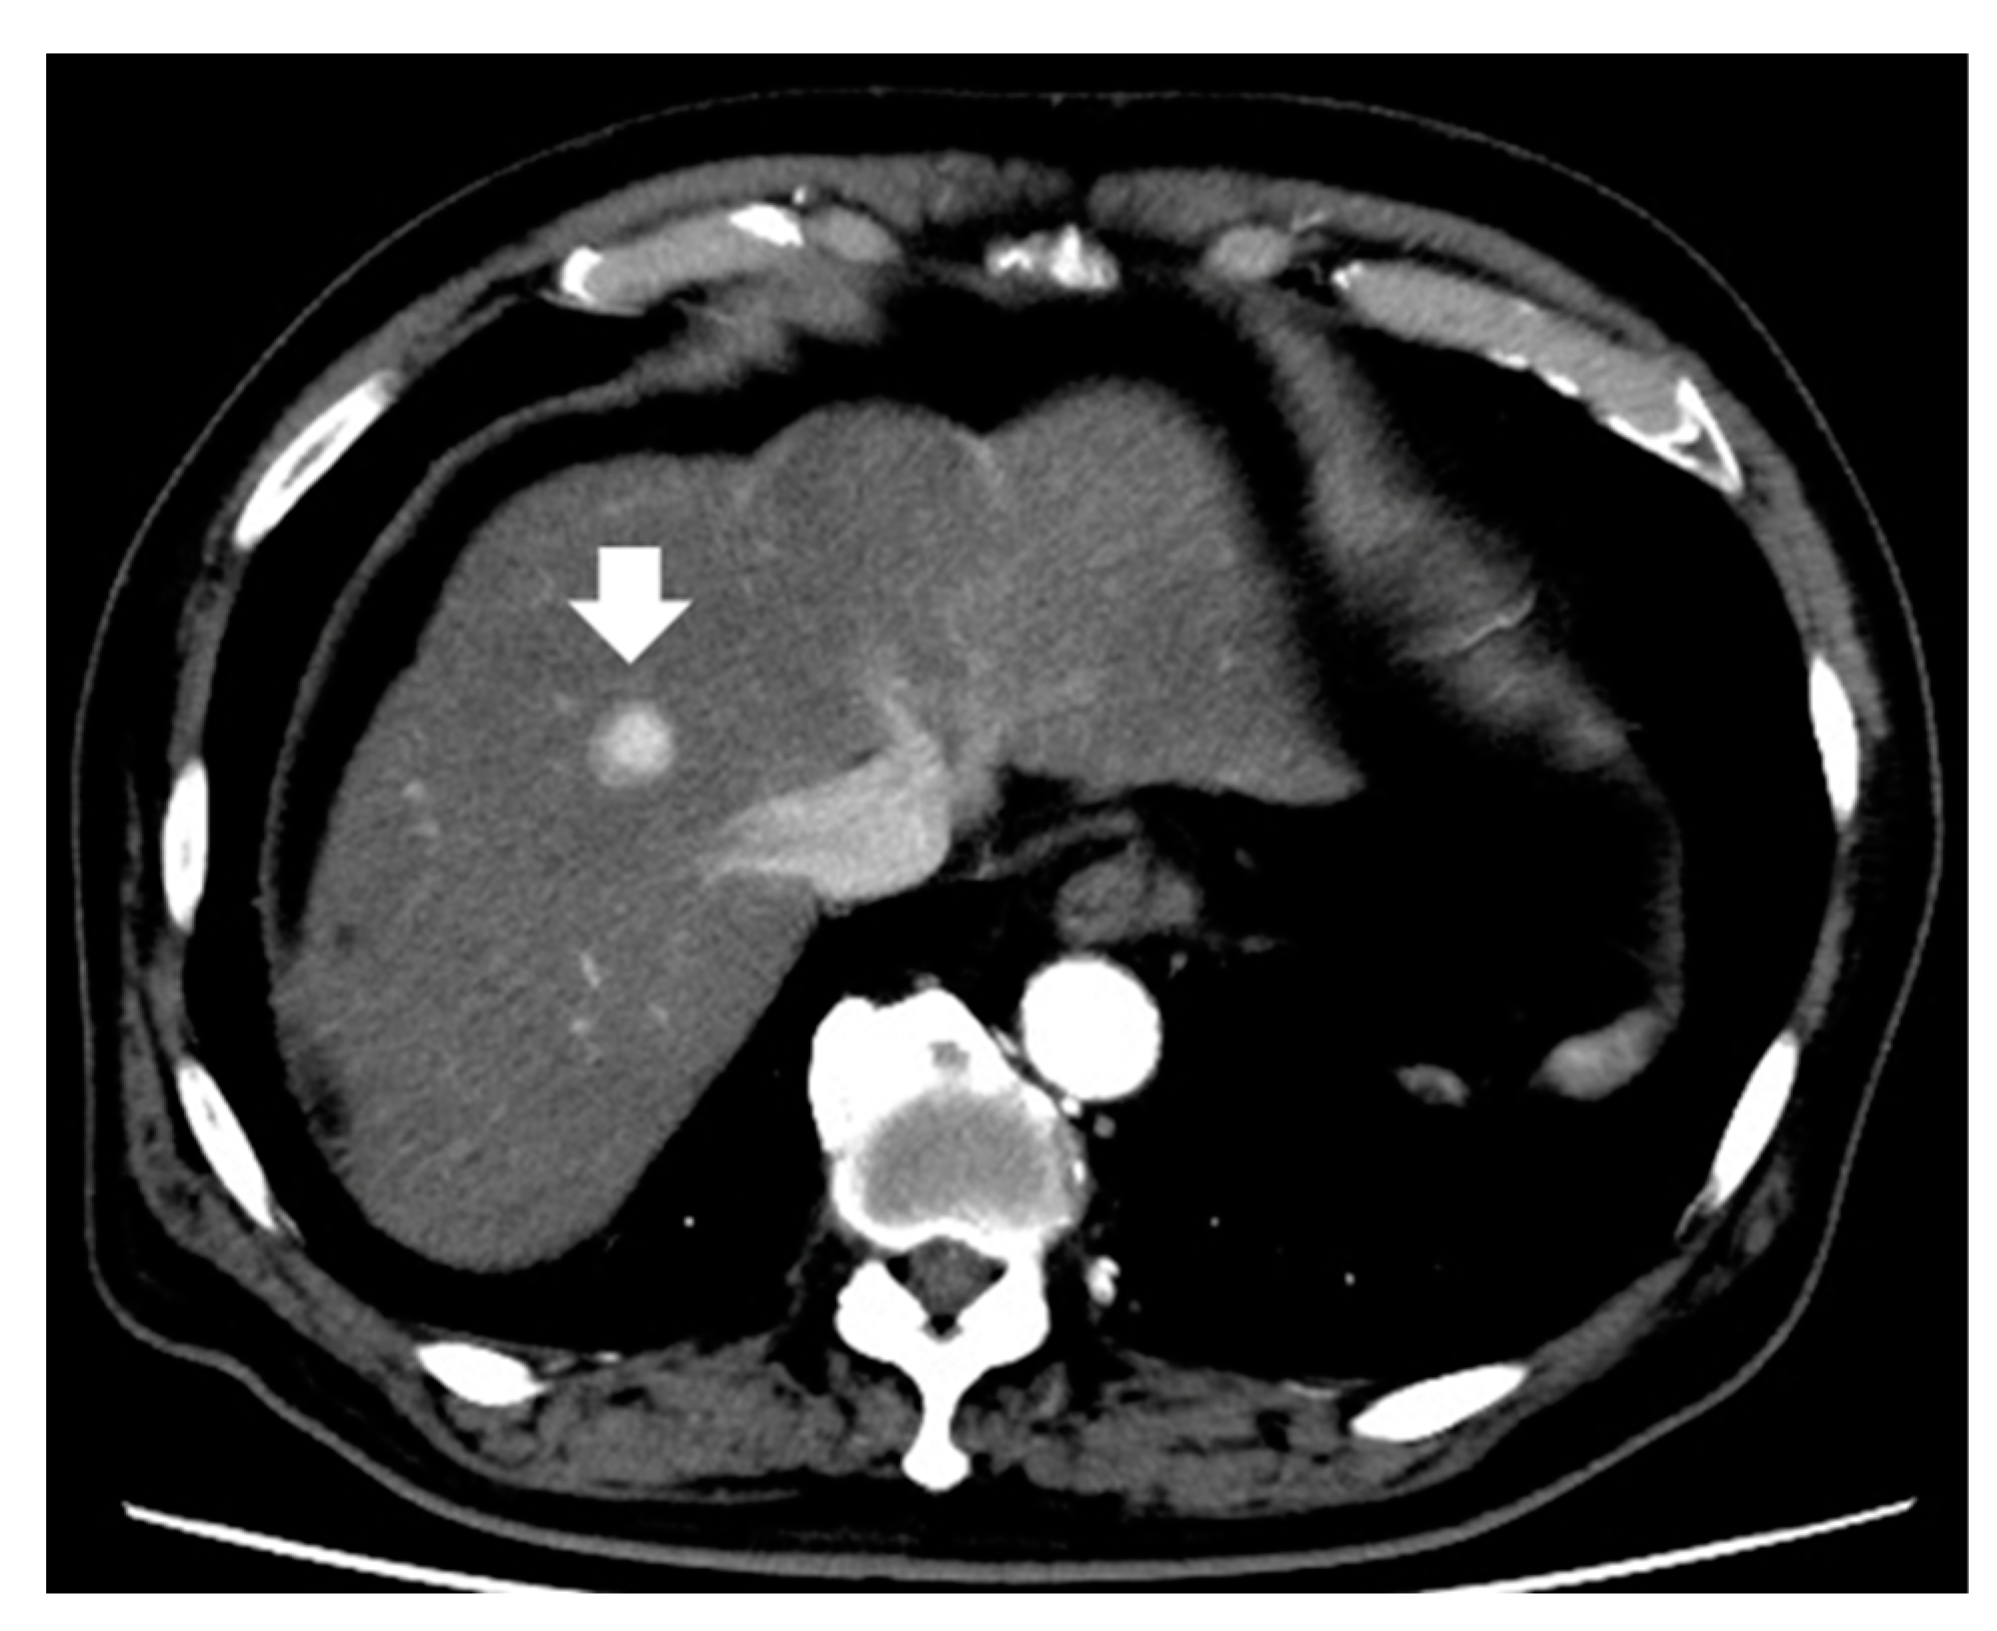

4. Magnetic Resonance Imaging

4.1. Enhancement Pattern in the Hepatobiliary Phase

4.2. Enhancement Pattern in the Arterial Phase

4.3. Diffusion-Weighted Imaging

- Lee, S.; Kim, S.H.; Lee, J.E.; Sinn, D.H.; Park, C.K. Preoperative gadoxetic acid-enhanced MRI for predicting microvascular invasion in patients with single hepatocellular carcinoma. J. Hepatol. 2017, 67, 526–534. [Google Scholar] [CrossRef]

- Lee, S.; Kang, T.W.; Song, K.D.; Lee, M.W.; Rhim, H.; Lim, H.K.; Kim, S.Y.; Sinn, D.H.; Kim, J.M.; Kim, K.; et al. Effect of Microvascular Invasion Risk on Early Recurrence of Hepatocellular Carcinoma After Surgery and Radiofrequency Ablation. Ann. Surg. 2021, 273, 564–571. [Google Scholar] [CrossRef]

- Hu, Z.; Yu, N.; Wang, H.; Li, S.; Yan, J.; Zhang, G. Pre-radiofrequency ablation MRI imaging features predict the local tumor progression in hepatocellular carcinoma. Medicine 2020, 99, e23924. [Google Scholar] [CrossRef] [PubMed]

- An, C.; Kim, D.W.; Park, Y.N.; Chung, Y.E.; Rhee, H.; Kim, M.J. Single Hepatocellular Carcinoma: Preoperative MR Imaging to Predict Early Recurrence after Curative Resection. Radiology 2015, 276, 433–443. [Google Scholar] [CrossRef] [PubMed]

- Chiang, J.; Cristescu, M.; Lee, M.H.; Moreland, A.; Hinshaw, J.L.; Lee, F.T.; Brace, C.L. Effects of Microwave Ablation on Arterial and Venous Vasculature after Treatment of Hepatocellular Carcinoma. Radiology 2016, 281, 617–624. [Google Scholar] [CrossRef] [PubMed]

- Kierans, A.S.; Leonardou, P.; Hayashi, P.; Brubaker, L.M.; Elazzazi, M.; Shaikh, F.; Semelka, R.C. MRI findings of rapidly progressive hepatocellular carcinoma. Magn. Reson. Imaging 2010, 28, 790–796. [Google Scholar] [CrossRef]

- Rhee, H.; An, C.; Kim, H.Y.; Yoo, J.E.; Park, Y.N.; Kim, M.J. Hepatocellular Carcinoma with Irregular Rim-Like Arterial Phase Hyperenhancement: More Aggressive Pathologic Features. Liver Cancer 2019, 8, 24–40. [Google Scholar] [CrossRef]

- Petukhova-Greenstein, A.; Zeevi, T.; Yang, J.; Chai, N.; DiDomenico, P.; Deng, Y.; Ciarleglio, M.; Haider, S.P.; Onyiuke, I.; Malpani, R.; et al. MR Imaging Biomarkers for the Prediction of Outcome after Radiofrequency Ablation of Hepatocellular Carcinoma: Qualitative and Quantitative Assessments of the Liver Imaging Reporting and Data System and Radiomic Features. J. Vasc. Interv. Radiol. JVIR 2022, 33, 814–824.e813. [Google Scholar] [CrossRef]

- Grazioli, L.; Olivetti, L.; Fugazzola, C.; Benetti, A.; Stanga, C.; Dettori, E.; Gallo, C.; Matricardi, L.; Giacobbe, A.; Chiesa, A. The pseudocapsule in hepatocellular carcinoma: Correlation between dynamic MR imaging and pathology. Eur. Radiol. 1999, 9, 62–67. [Google Scholar] [CrossRef]